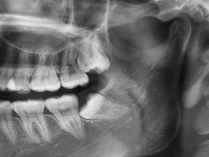

②生长位置不正智齿长歪挤压邻牙或出现阻生智齿。

智齿长歪和相邻的恒牙挤着生长,会不易清洁,当生长空间不足时,还会出现严重的牙龈肿胀,甚至导致前牙歪斜、排列拥挤,牙列不齐阻生智齿(智齿刺客)通常都埋在牙槽骨里面,非常容易被忽略,需要通过拍牙片诊断。